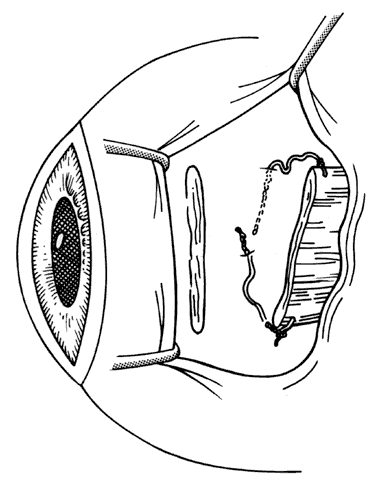

The incision should provide sufficient exposure and should be one the surgeon feels comfortable using. Our preference is to attempt to use a cul-de-sac incision whenever possible. This incision eliminates dissection through conjunctiva and anterior Tenon's capsule. When corrections require surgery on the superior rectus, conjunctiva is preserved for the remote possibility that a glaucoma filtering procedure may be required in the future (Figs. 13 and 14). The conjunctival incision can usually be made either through the old incision or just posterior to it.

Fig. 13. Incision is made through the conjunctiva. Conjunctiva is then dissected free from any adherent Tenon's capsule that overlies the site of the old muscle insertion. A blunt-tip Wescott scissors facilitates this dissection.

Fig. 14. This dissection is carried past the insertion until a hook is able to be passed under the muscle without restriction.